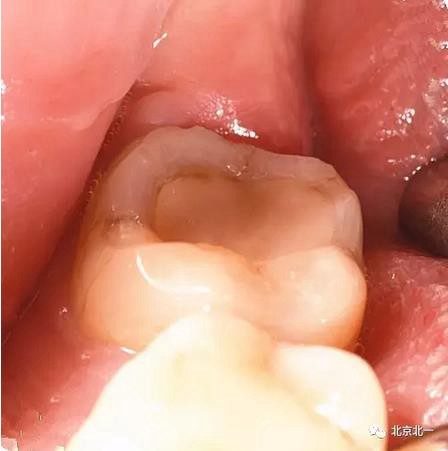

病例資料:一般情況,患者女性,28歲, 主訴:要求拔右側下頜智齒,檢查:右側下頜第三磨牙未見萌出, 拍片如圖。

圖五:臨床所見